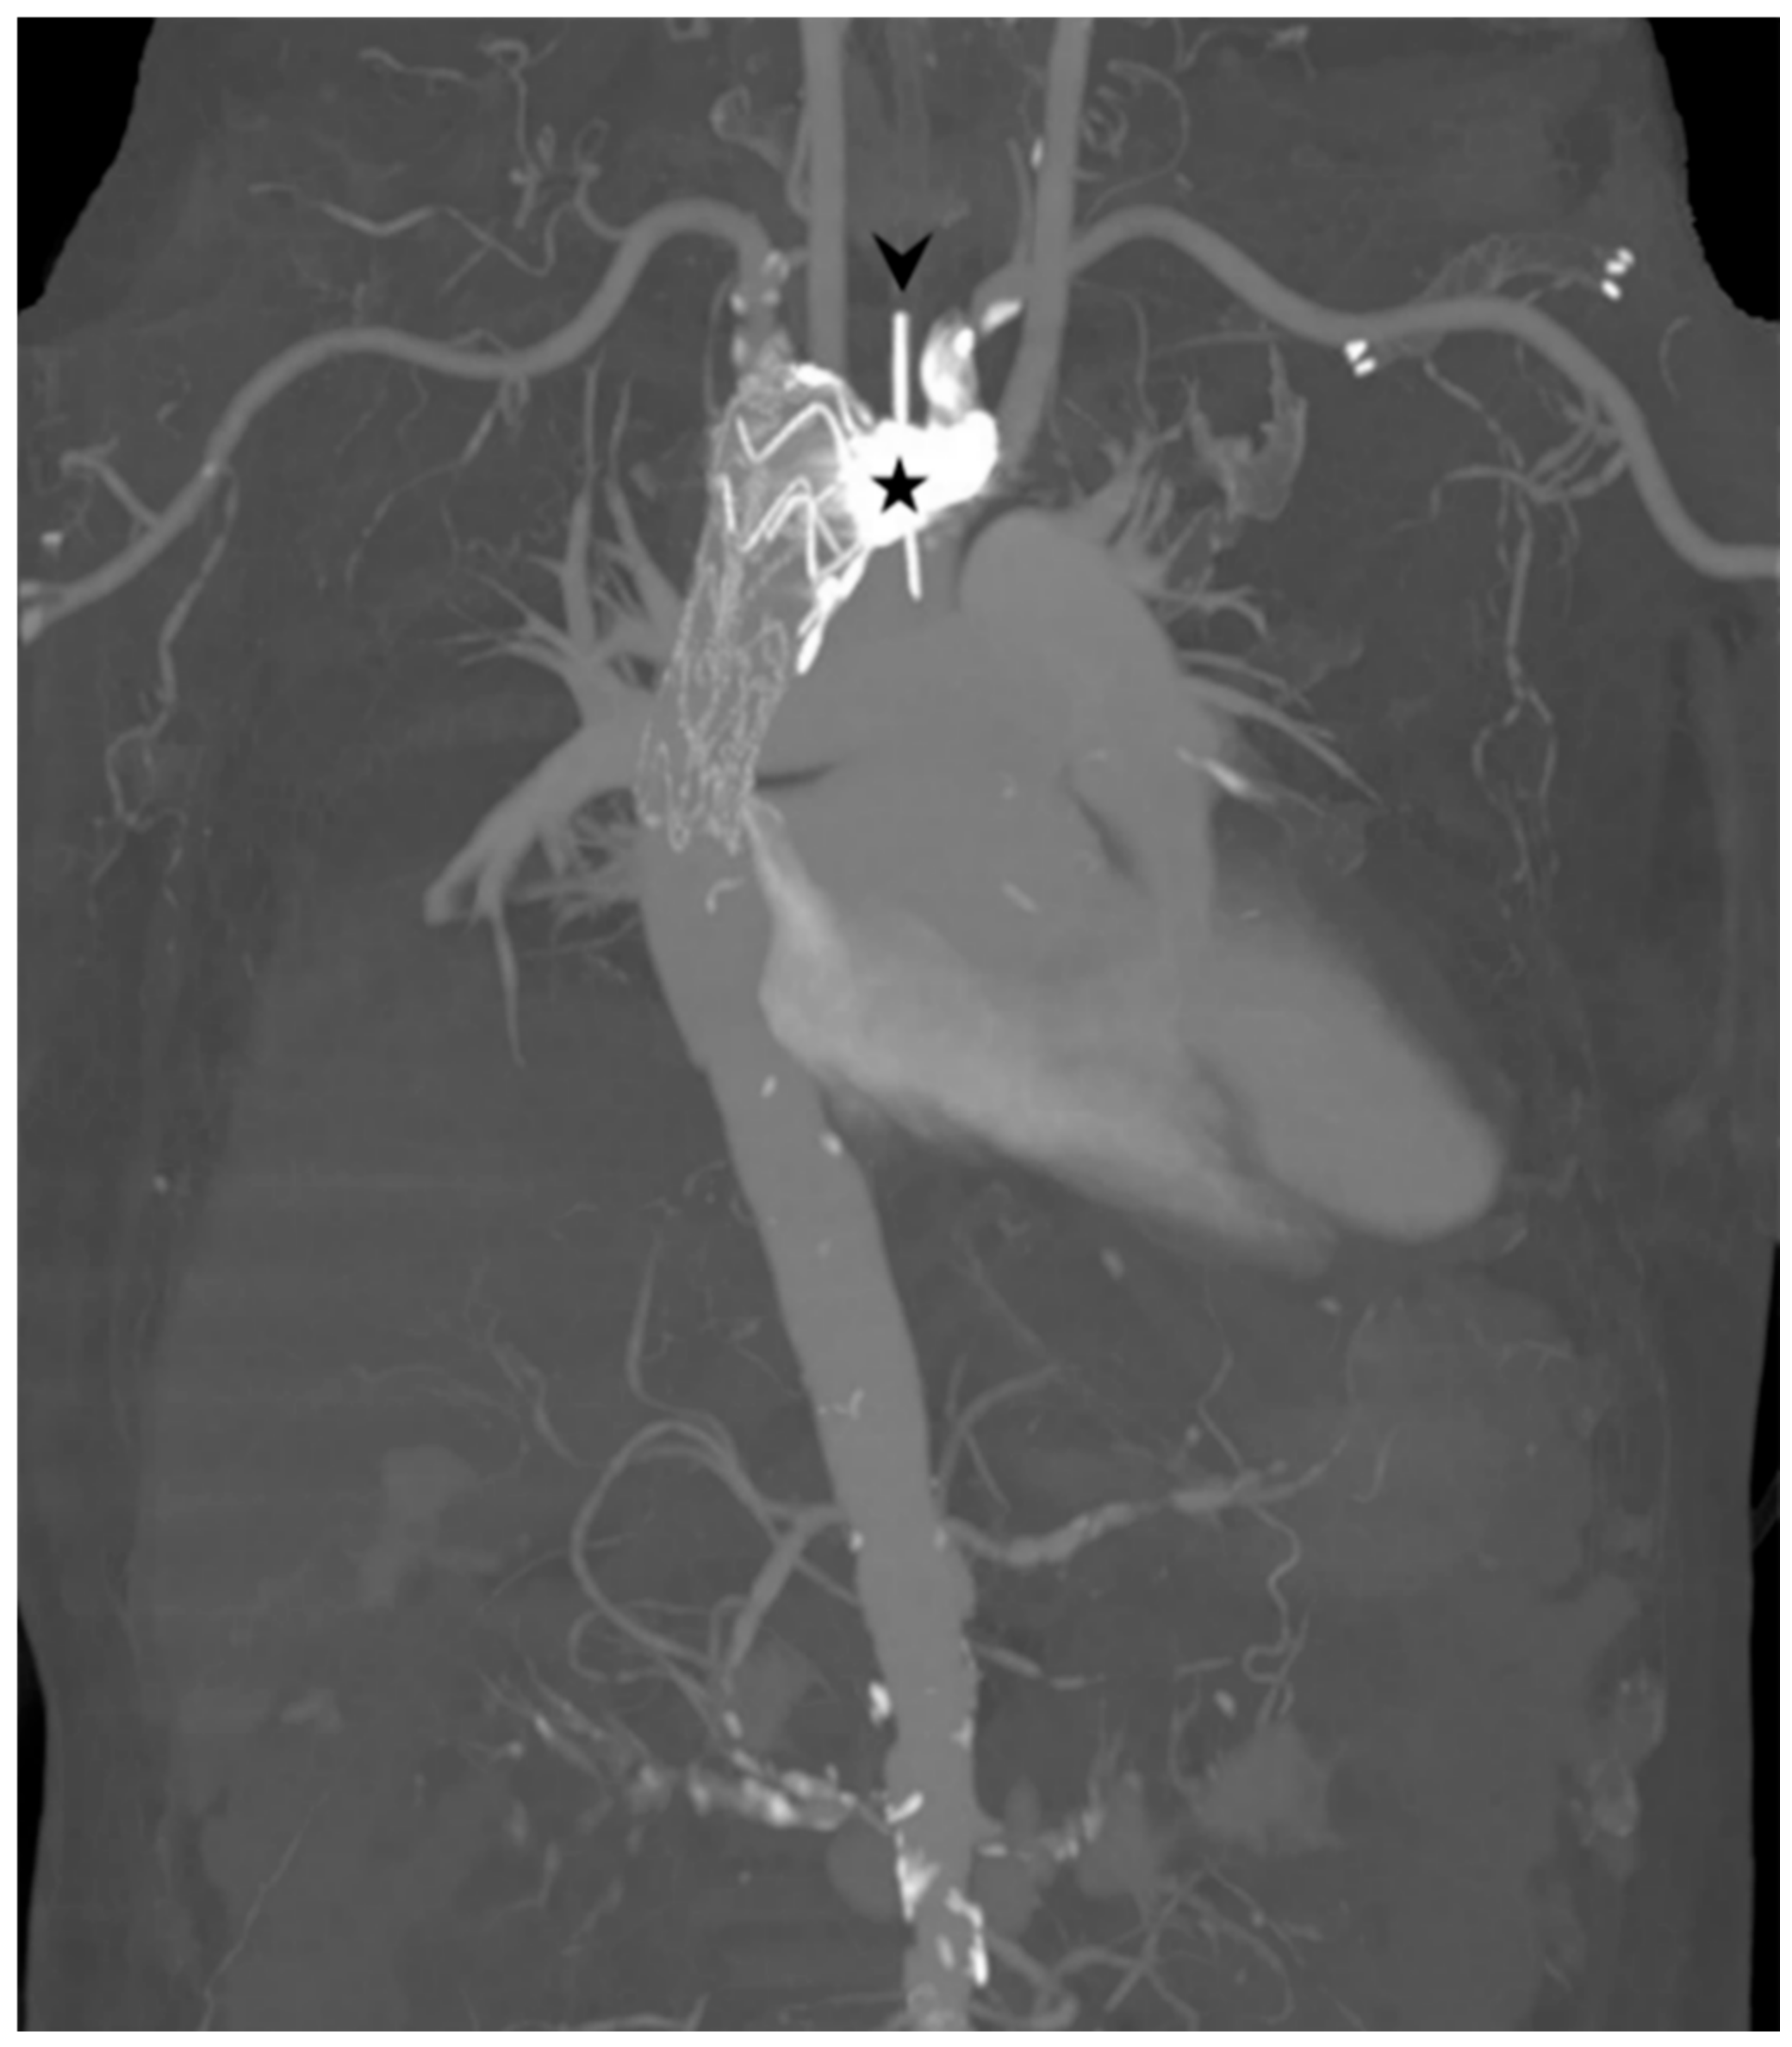

2. Case Report